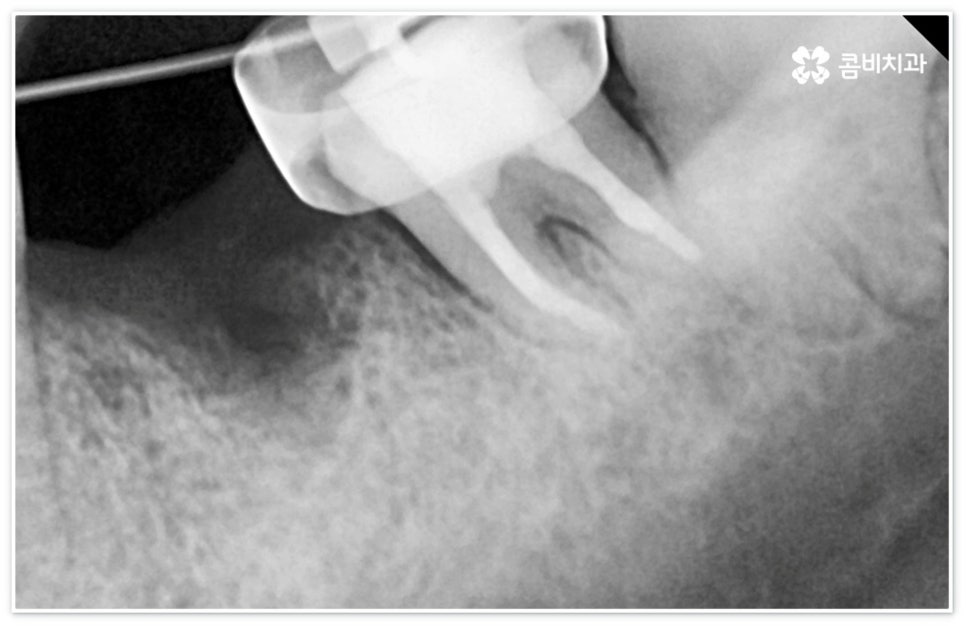

신경치료는 일견 간단해 보일 수 있으나 사람의 신경이 매우 얇고 또한 환자분들마다 신경관의 개수와 모양이 다 다르기 때문에 오염된 부위를 끝까지 깨끗하게 제거하기 위해서는 매우 섬세하고 뛰어난 기술력을 요하므로 다양한 임상 경험을 통해 풍부한 노하우를 가지고 있는 의료진과 함께 하실 필요가 있습니다.

신경치료는 오염된 치수 조직을 제거하여 감염이 더이상 진행되지 않도록 하고 치과용 충전재로 내부를 빈틈없이 채운 후 크라운 보철물을 씌워 남아있는 자연 치아를 쓸 수 있도록 하는 치료이기 때문에 그 과정에서 치아 깊숙한 곳까지 기구로 파고들어 가므로 주변 치아 조직이 예민해지면서 치료 후 며칠에서 길게는 몇 주까지 신경치료통증 을 느끼실 수 있는데요.

혹여 미세한 부근관의 염증을 놓치거나 사후 외부 원인으로 2차 감염이 일어나는 경우 신경치료통증 이 오래 지속될 수 있으니 며칠이 지났음에도 욱신거림이 줄어들기는 커녕 점차 심해진다는 느낌이 있다면 다시 한 번 치과로 내원하셔서 꼼꼼하게 검진 후 필요한 치료를 받으시는 게 좋을 거예요. 상황에 따라 재신경치료를 진행해야 할 수도 있고 좀 더 지켜보면서 발치가 불가피하지는 않은지 신중하게 판단해야 할 수도 있는데요. 예를 들어 만약 신경치료통증 의 원인이 치료 전부터 치아 뿌리에 생겼던 미세한 균열 때문이라면 치료 받은 치아로 씹을 때 통증이 지속적으로 나타날 수 있고 재신경치료 등으로 이를 살릴 수 없으므로 이 통증이 일상생활에 큰 영향을 주지 않을 경우 최대한 사용하는 데까지 사용을 하다가 임플란트 치료를 권장 드리고 있으나 증상이 심할 경우 바로 발치를 해야 하며, 매우 낮은 확률이긴 하지만 신경관 내부 뿐 아니라 외부에도 세균 군집이 생겨 치아 뿌리 끝 염증이 나아지다가 다시 악화된 상황이라면 역시 약 처방 등으로 신경치료통증 을 잡을 수 없고 발치 후 임플란트 식립을 통해 치료해야 할 거예요.